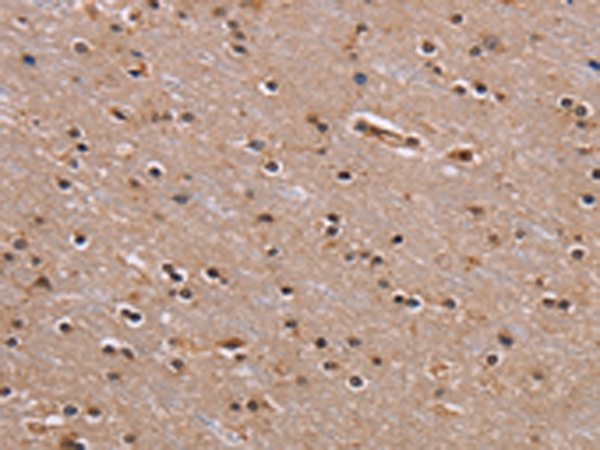

分类: 科研抗体货号: P01604别名: CN1; CNI; CN-I; CN1A; CN-IA应用: IHC反应种属: Human, Mouse